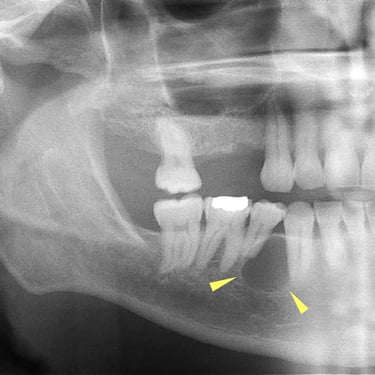

Quiste dentígero

Un quiste dentígero es un saco lleno de líquido que se forma alrededor de la corona de un diente no erupcionado.

Los pacientes pueden notar una hinchazón indolora en la mandíbula.

El tratamiento incluye la extirpación quirúrgica del quiste y, a veces, la extracción del diente involucrado.